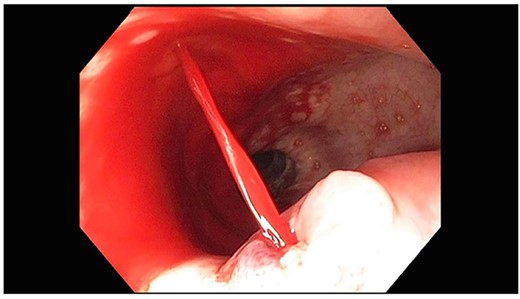

A 71-year-old male with past medical history of type 2 diabetes and hypertension presented to the emergency department at St. Joseph’s University Medical Center with severe respiratory distress. On nonrebreather, the patient’s oxygen saturation was 49%. The patient was subsequently intubated. Evaluation revealed pneumonia secondary to COVID-19 leading patient to be intubated on ventilator support for 4 weeks. During this time patient was maintained on enteral feeding through nasogastric tube, and was on gastrointestinal prophylaxis Protonix 40 mg daily for the duration of his admission. Ultimately, the patient made full recovery and was sent home; however, approximately 3 weeks later, he presented to the emergency department due to syncope. The patient experienced large-volume bright red hematemesis. He became hypotensive and was transfused three units of packed red blood cells and started on pressors. The patient was intubated and transferred to the intensive care unit (ICU) with acute blood loss anemia and hypovolemic shock. Here, an esophagogastroduodenoscopy (EGD) was performed revealing midesophageal bleed (Fig. 1). Hemostasis was achieved with clipping; however, post-procedurally, the patient again became hypotensive. Repeat EGD showed a nonbleeding esophageal ulcer with three clips in good position (Fig. 2). Computed tomography (CT) angiogram of the thorax was performed revealing an actively bleeding aberrant right subclavian artery perforating into the esophagus (Figs 3 and 4). The right subclavian artery was noted to be of normal caliber without ectasia or aneurism and the esophagus was free of any other pathology. Thoracic and vascular surgery were consulted; however, the bleed was deemed of nonsurvivable pathology due to comorbidities and current clinical status. Ultimately, the family of the patient decided to withdraw care and the patient passed.

CT thoracic angiogram showing actively bleeding aberrant right subclavian artery perforating into the esophagus (red arrow).